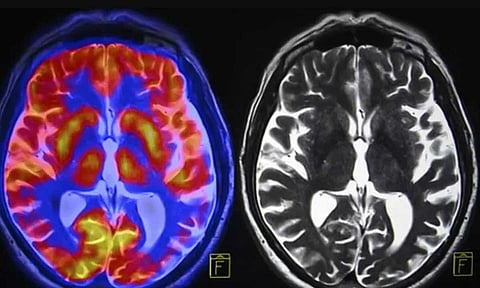

وقارن الباحثون فحوصات التصوير بالرنين المغناطيسي لأكثر من 80 شاباً قبل كورونا بسنوات وفي أثناء وبعد فيروس كورونا، فوجدوا أن التغيرات الجسدية في الدماغ التي حدثت خلال فترة المراهقة، مثل ترقّق القشرة ونمو الحُصين واللوزة، كانت أكبر في فترة ما بعد الإغلاق، مقارنةً بمجموعة ما قبل الجائحة، ما يشير إلى تسريع مثل هذه العمليات، بعبارة أخرى تقدّمت أدمغتهم بشكل أسرع.